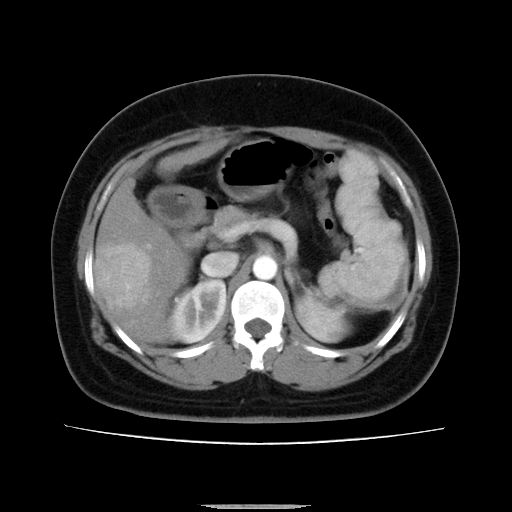

标题: CT14225:女性46岁。当地B超示肝内占位,来我院作CT检查。请 [打印本页]

标题: CT14225:女性46岁。当地B超示肝内占位,来我院作CT检查。请

速升速降,支持肝癌.脾体积增大,形态欠规整,请询问病史是否做过脾动脉栓塞.

速升速降,支持肝癌可能。

右叶肝癌灶;慢性胆囊炎,不除外占位;;副脾可能性

快进快出,符合肝癌表现-----------

肝内结节强化特点符合原发性肝癌表现,脾脏改变考虑为增大及先天发育所致。

动脉期病原灶明显强化高于肝密度且中央有无强化区,静脉期强化程度下降明显,延迟低于肝密度,考虑肝腺瘤可能性大,

肝内结节强化特点:快进快出符合原发性肝癌表现

此患者虽然符合快进的特点,却不符合快出的特点,因为门脉期几乎是等密度,不符合肝癌的增强表现,所以我考虑肝局灶性结节增生可能性大